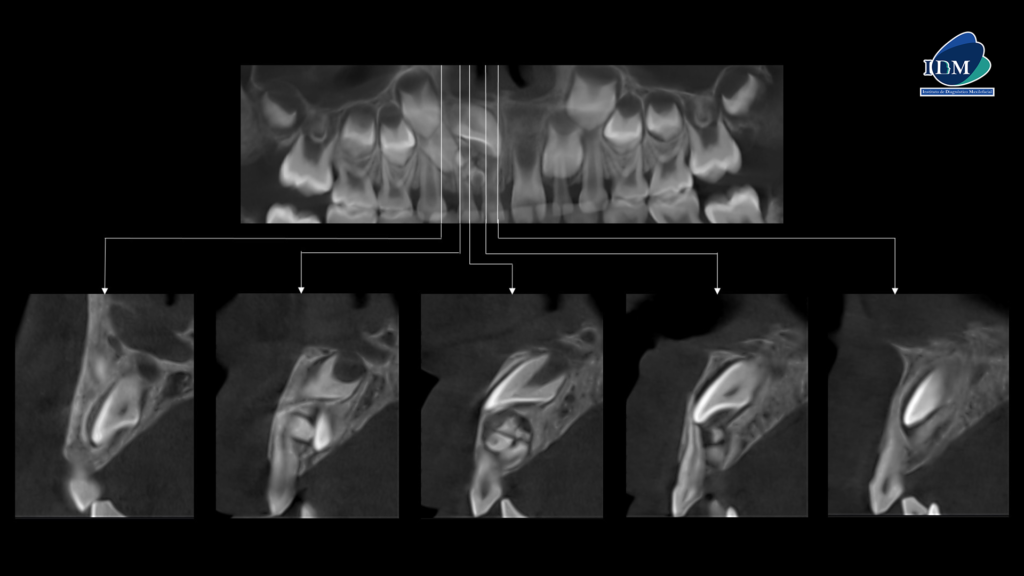

A la evaluación de la tomografía volumétrica (CBCT) en los cortes axiales (Figura 2) y transaxiales(Figura 3), se aprecia múltiples dentículos circunscrito de un halo hipodenso, localizada en palatino del tercio apical y medio de piezas 52-51, que ocasiona el desplazamiento de la pieza 11 hacia cefálico y adelgazamiento de la tabla ósea palatina En las reconstrucciones 3D se representa odontoma compuesto. (Figura 4).

CORTES TRANSAXIALES